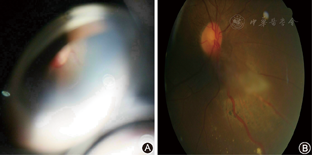

眼底镜检查(图5):右眼鼻下方靠前血管母细胞瘤,直径0.5 cm,可见粗大的滋养血管,黄斑水肿混沌,液体渗出。